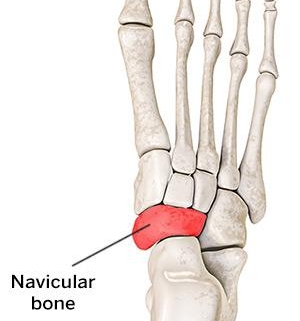

The foot is a complex structure, composed of multiple bones, and one lesser-known bone is the accessory navicular. Not everyone has this extra bone, but those who do may experience discomfort or pain, known as accessory navicular problems or syndrome. This condition is relatively rare, affecting about 2 to 14 percent of the population.

There are generally three types of accessory navicular bones, each with unique characteristics:

1. Type 1 – Os Tibiale Externum: A relatively small, isolated bone just above the arch on the inside of the foot.

2. Type 2 – Triangular or Heart-Shaped Bone: This type of accessory navicular bone is connected to the navicular bone by fibrous tissue and is the most common type associated with accessory navicular problems.

3. Type 3 - Prominent Navicular Tuberosity: This is essentially an enlarged navicular bone, rather than an additional accessory bone.